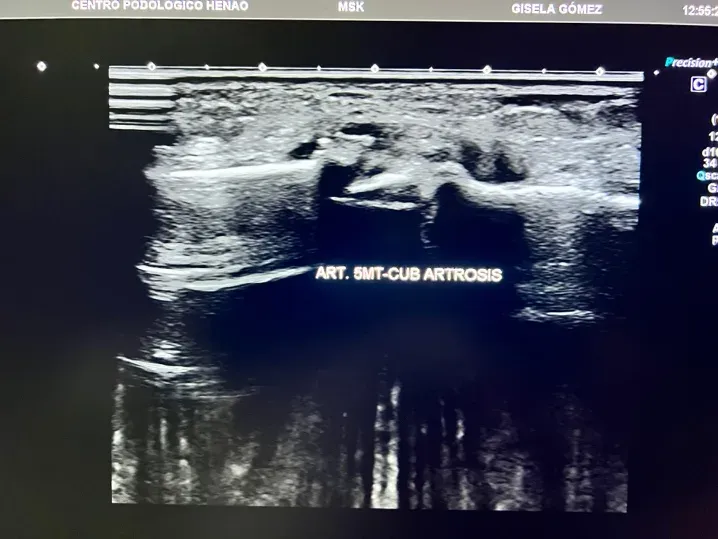

- Articulaciones del mediopié: afectan a la zona central del pie y pueden limitar actividades tan básicas como caminar en terreno irregular o subir cuestas.

En el contexto de la artrosis del pie, la ecografía detecta:

- Cambios en el cartílago articular: antes de que la radiografía muestre nada

- Irregularidades en la superficie articular: signos tempranos de desgaste

- Inflamación articular (sinovitis): presencia de líquido o engrosamiento de la membrana sinovial

- Derrame articular: acumulación de líquido dentro de la articulación

- Osteofitos en fases iniciales: formaciones óseas que aún no son visibles en radiografía

- Estado de los tejidos blandos periarticulares: cápsula, ligamentos, tendones adyacentes

Figura 3: Ecografía de una articulación del pie con artrosis. Se observan irregularidades en el cartílago, estrechamiento del espacio articular y formación de osteofitos. Compara con la Figura 2 para apreciar la diferencia.